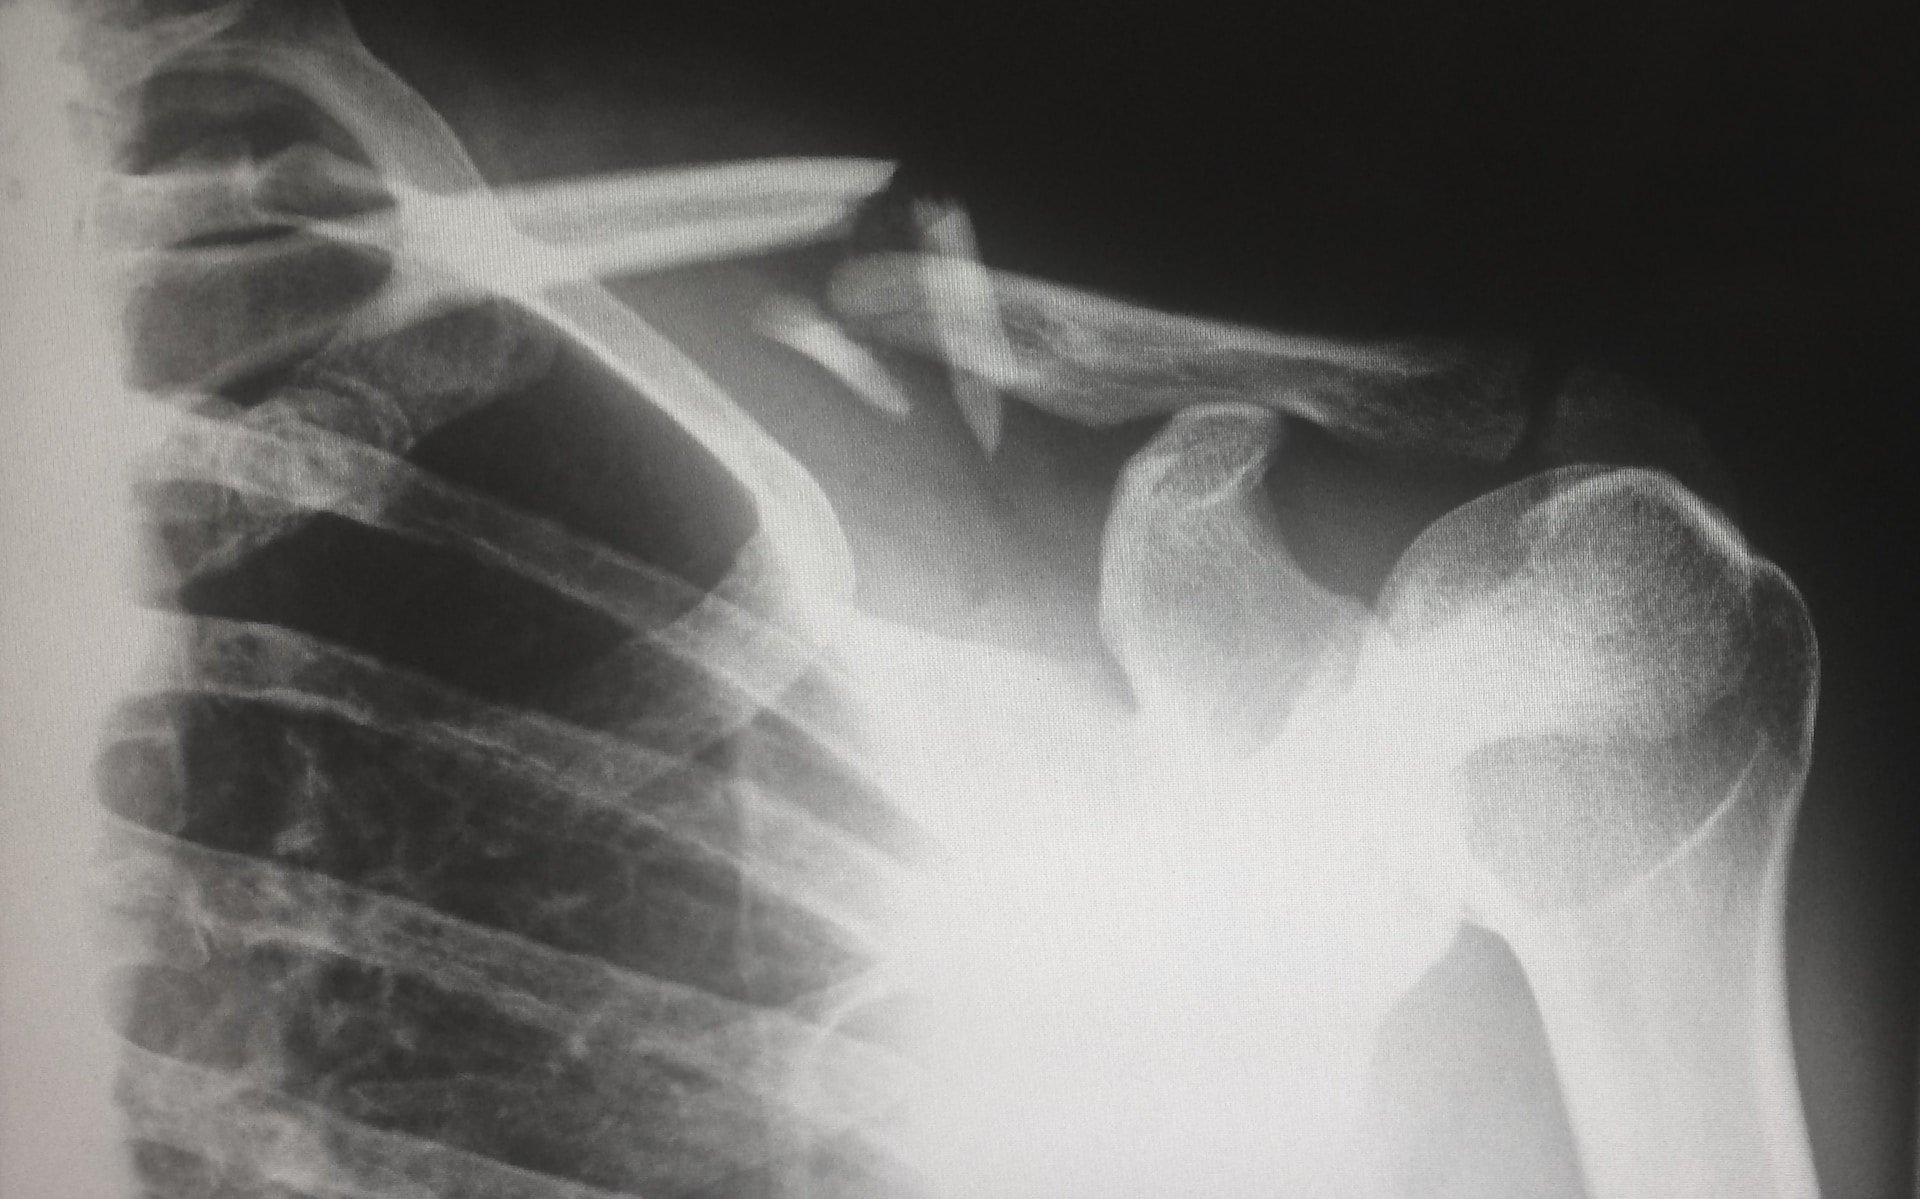

When I got to the ER the doctor came and checked to see where I was broken. They took me to have a CT scan and made an x-ray. I asked if I could have something for pain. Instead of a shot, the nurse gave me two Tylenol.

It was my right arm that was broken and, of course, I’m right handed. I’ve been pretty helpless since I got home, and I haven’t been able to do anything. Honey has been taking care of me because there is nobody else.